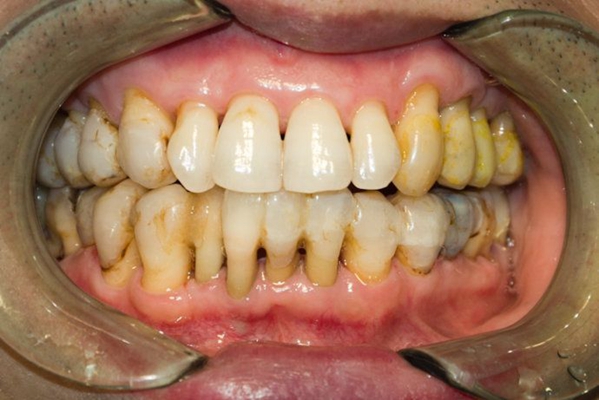

牙周炎圖片

牙周袋 (7)